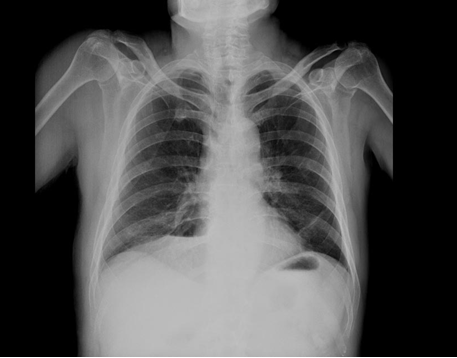

Simultaneously, rigid fluid restriction was performed in the patient thought to have SIADH. Serum Na+ value reached up to 137 mEq/L (137 mmol/L) within few days. There was no abnormal finding on preoperative chest radiograph (Figure 2). However, thoracic and abdominal CT scan was re-evaluated in the context of malignancy screening. On thoracic CT scan, diffuse thickening (up to 1–1.5 cm) with irregular contours were observed at the level of hilus on the left, while isodense and hypodense lesions were seen in liver on abdominal CT scan. Diffuse metastatic disease was found in the patient by positron emission tomography (PET) scan and magnetic resonance imaging (MRI) scan. SCLC diagnosis was made by biopsy samples obtained from liver and the patient was referred to oncology department.

Figure 2: Postoperative lung image: Postoperative full expanded lung.